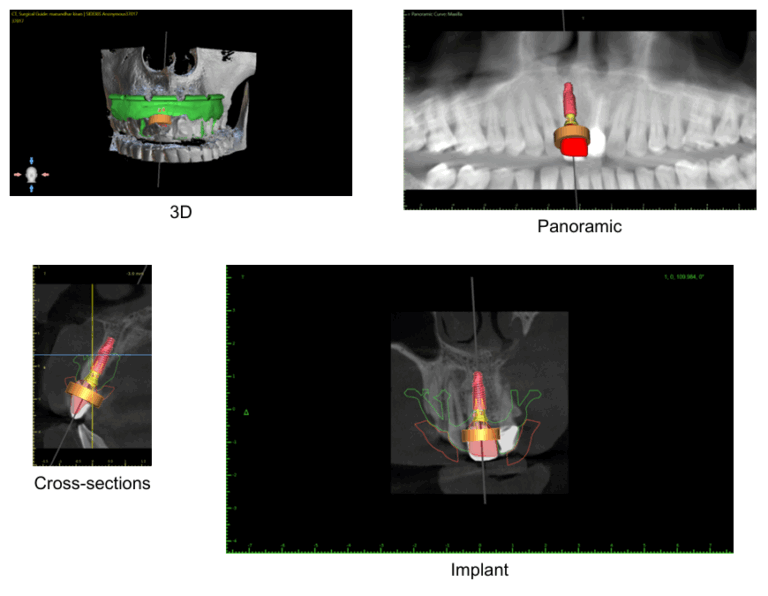

Figure: Digital Implant Planning

Since the front tooth area is highly visible, precision was essential. We performed: